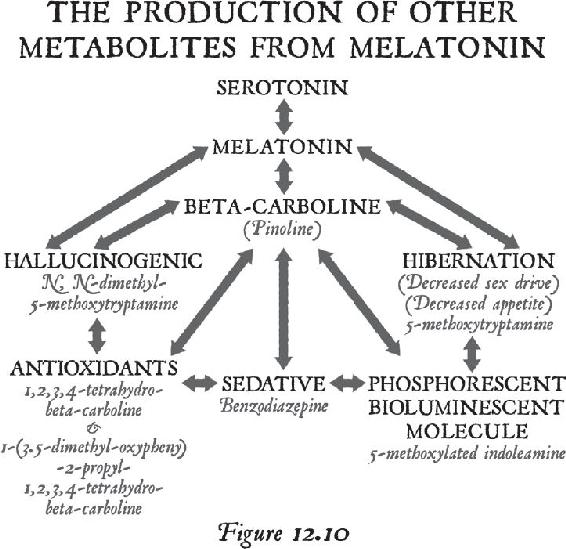

Once you are beyond your associations to this material world and you are in the unified field—chock-full of infinite possibilities—biological systems exist for taking that energy that’s beyond the vibration of matter and turning it into imagery in the brain. That’s where the pineal gland comes in, the subject of Chapter 12. Think of your pineal gland—a tiny gland perched in the central back area of your brain—as an antenna that can transduce frequencies and information and turn them into vivid imagery. When you activate your pineal gland, you are going to have a full-on sensory experience without your senses. That internal event will be more real to you in your mind while your eyes were closed than any past external experience you’ve ever had. In other words, in order to lose yourself fully in the inward experience, it has to be so real that you are there. When this happens, this little gland transmutes melatonin into some very powerful metabolites that cause you to have that type of experience. We will study the properties of this gland and then you will learn how to activate it.